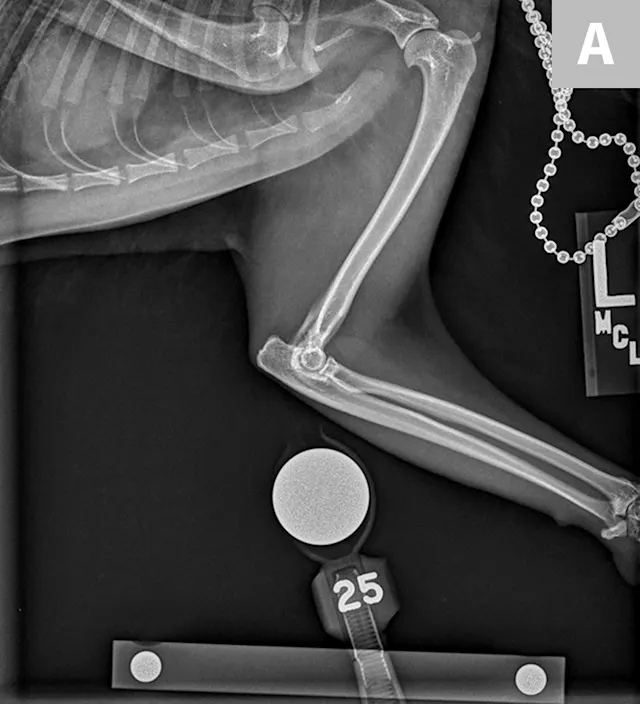

FIGURE 3

Lateral (A) and dorsoventral (B) views of the pelvis. Figure A shows a moderate amount of the smoothly marginated, bridging, bony proliferations surrounding the 2nd through 5th coccygeal vertebrae. A moderate amount of kyphosis is present on the tail, centered in the bony proliferation. A mild amount of irregularly marginated bony proliferation is present surrounding the facet joint of the C5-C6 intervertebral disk space. Figure B shows poor coverage of the right femoral head by the acetabulum. A moderate amount of irregularly marginated bony proliferation is present on the cranial and caudal aspects of the acetabulum and femoral neck. There is decreased soft tissue associated with the left pelvic limb as compared with the right. A small osteophyte on the left cranial acetabulum can be noted. Image courtesy of Dr. Karen Perry. Interpretation: Chronic, healed caudal vertebral fracture, C2-C4. Moderate, right coxofemoral osteoarthritis and mild left coxofemoral osteoarthritis